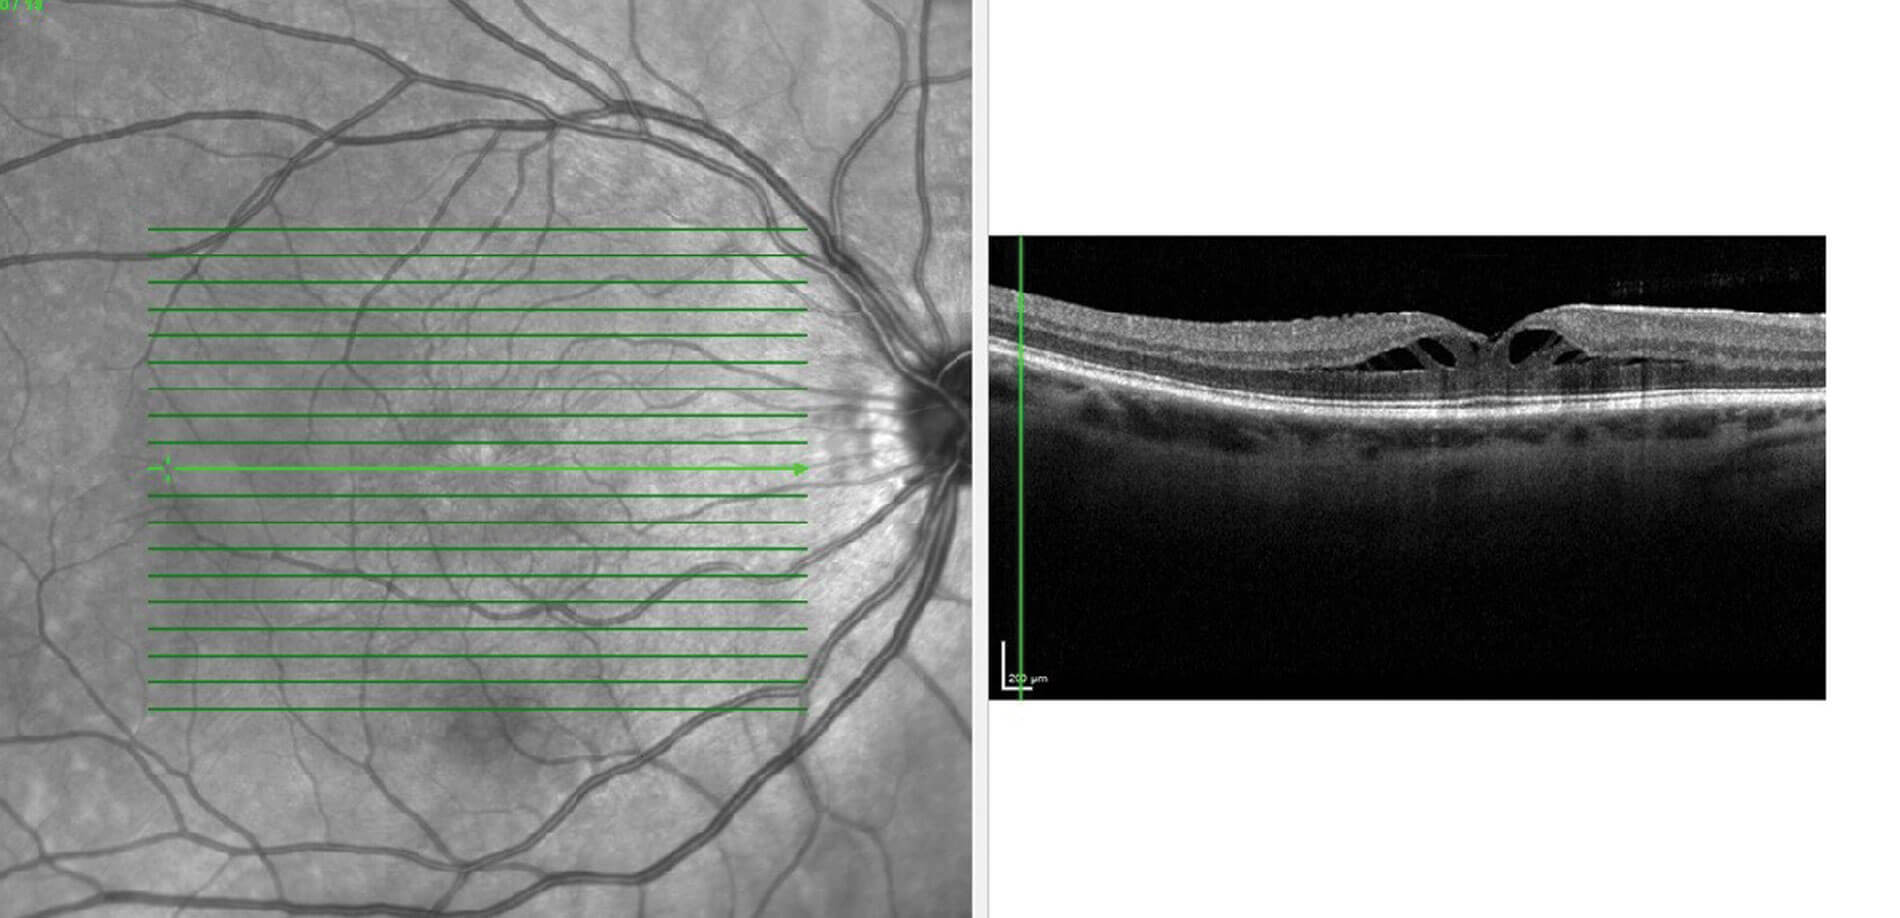

Figure 3: OCT macula of the right eye with foveal schisis.

Myopic traction maculopathy (MTM), also known as foveal schisis was first described by Takano and Kishi in 1999, when they noticed a break in the foveal region in patients with posterior staphyloma [20]. The pathogenesis for development of foveal schisis was due to the abnormal elongation of the sclera in the presence of different stretching capacity of choroid and the retina. This causes parallel and perpendicular stretching force in the retina leading to thickening of inner retinal layers and thinning of outer retinal layers (Figure 3) Other contributing factors for fovealschisis could be inter-limiting membrane rigidity, vitreomacular traction, and epiretinal membrane [20]. Raizada, et al. described an OCT-based classification of MTM: